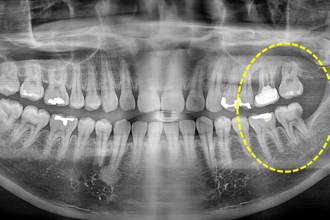

임플란트